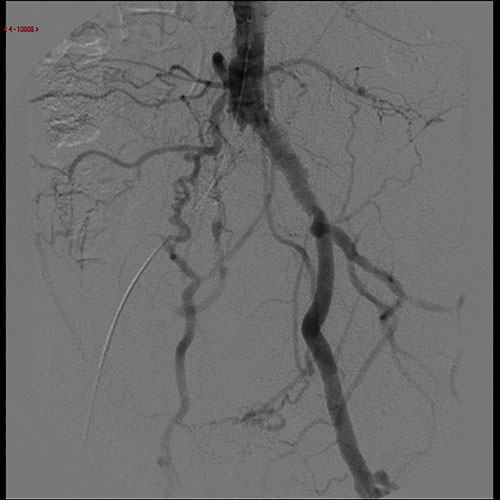

Απεικονιστικές εξετάσεις για τη διερεύνηση της διαλείπουσας χωλότητας αποτελούν το έγχρωμο duplex (triplex), η αξονική αγγειογραφία, η μαγνητική αγγειογραφία και η ψηφιακή αφαιρετική αγγειογραφία.

Σε περιπτώσεις διαλείπουσας χωλότητας μη περιοριστικού τύπου συνήθως η θεραπεία είναι συντηρητική. Αυτή περιλαμβάνει φαρμακευτική αγωγή, ρύθμιση παραγόντων κινδύνου, διακοπή του καπνίσματος και επιτηρούμενο πρόγραμμα άσκησης. Σε περιπτώσεις κρίσιμης ισχαιμίας ή σοβαρής διαλείπουσας χωλότητας η αντιμετώπιση είναι συνήθως επεμβατική, είτε με αγγειοπλαστική με ή χωρίς stent, ή χειρουργική.